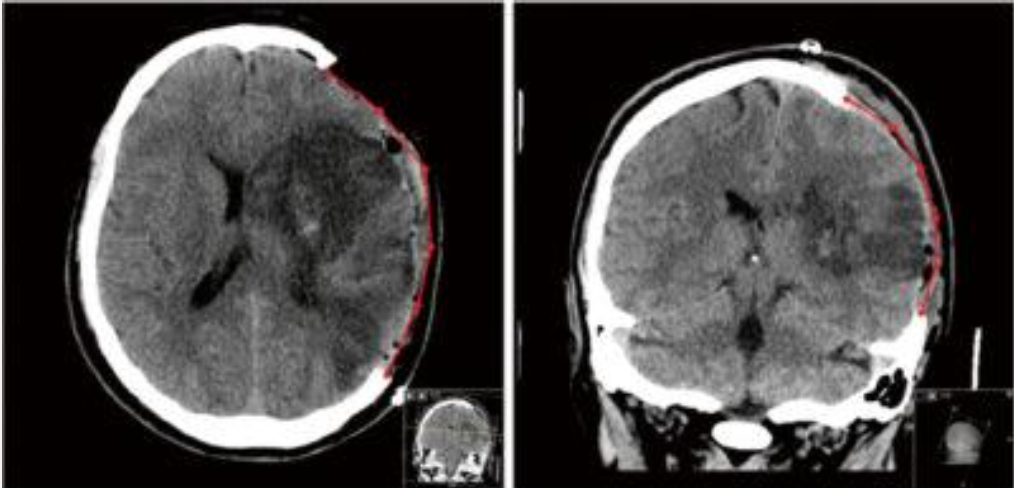

until u get a CT scan

MALIGNANT MCA

cerebral edema>> skull is closed box> raised ICP>> coma death!

decompressive hemicraniectomy

take some skull out> to allow a bit of brain to buldge out a relive ICP